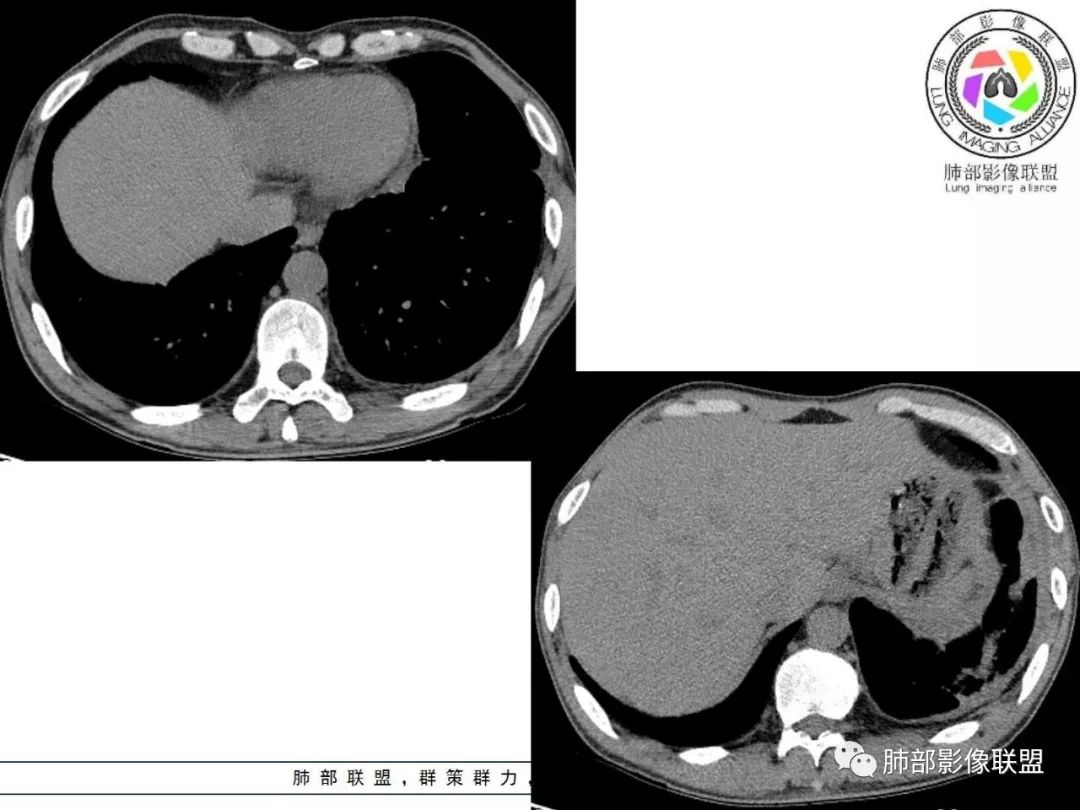

胸部CT:两肺弥漫病灶,磨玻璃影,少许实变,部分累及胸膜,磨玻璃区可见囊?少许胸腔积液,两肺可见结节,支气管血管束增粗,小叶间隔增厚,支气管走形有扭曲扩张,可见纤维化。气肿、大泡。考虑:感染性病变,PCP?查下HIV,CD4,G等。鉴别结核、结缔组织病肺浸润。

55多男性,发热为主诉,体温38℃-39℃多,午后及夜间发热为主,峰值40℃,伴黄痰,CRP高,血糖正常,胸部CT:两肺弥漫病灶,磨玻璃影,少许实变,部分累及胸膜,两肺可见结节,似可见树芽,支气管血管束增粗,小叶间隔增厚,见肺气肿、大泡。考虑感染性病娈,肺结核可能性大。

患者中年男性,发热1月,体温38℃-39℃,峰值40℃,无畏寒、寒战,伴黄痰,CRP升高明显,降钙素原稍升高,血沉、血糖正常。胸部CT:两肺弥漫病变,磨玻璃影+点片渗出,部分累及胸膜,磨玻璃区边界清楚,少许胸腔积液,两肺支气管血管束增粗,小叶间隔增厚,部分支气管走形有扭曲扩张,可见肺气肿、右肺尖肺大泡及部分纤维化改变。综合考虑:感染性病变。结核或PCP可能性大,鉴别风湿免疫、结缔组织疾病肺浸润和腺癌等恶性病变。

胸部CT:两肺弥漫病灶,中央间质分布为主,部分位于胸膜及叶间裂旁,磨玻璃影,斑片影,部分实性结节,肺气囊,支气管血管束增粗,小叶间隔增厚,叶间裂不均匀增厚,支气管走形有扭曲扩张,可见纤维化、气肿、大泡。考虑:LIP加MALT。鉴别PLCH、PCP、结核、结缔组织病肺浸润。

两肺弥漫性病变,沿支气管血管束分布,部分细支气管轻度扩张,两上中肺为主,部分累及胸膜下,部分磨玻璃影,部分纤维化,肺气肿肺大疱背景,胸膜增厚,少量积液,病程一月余,crp高反复发热,两肺门区增大钙化淋巴结,间质性疾病,考虑淋巴增殖性病变为主,结核可能性大,待鉴别NTM,结节病,LIP,PCP纤维化

2. 肺气肿背景(小叶中心性肺气肿);双肺多发病灶整体沿血管支气管束及胸膜下分布,以上叶及下叶背段分布为主,有实变及GGO,边界清楚,有树芽,小叶间隔及中央间质增厚,叶间裂见到多发结节,部分支气管不规则牵拉扩张,提示病灶纤维化明显,结合临床病史,考虑病灶为间质性感染,肺门及纵隔内有钙化淋巴结,小叶间隔结节,考虑淋巴道增值性疾病可能,综合常规要怀疑间质性肺结核。